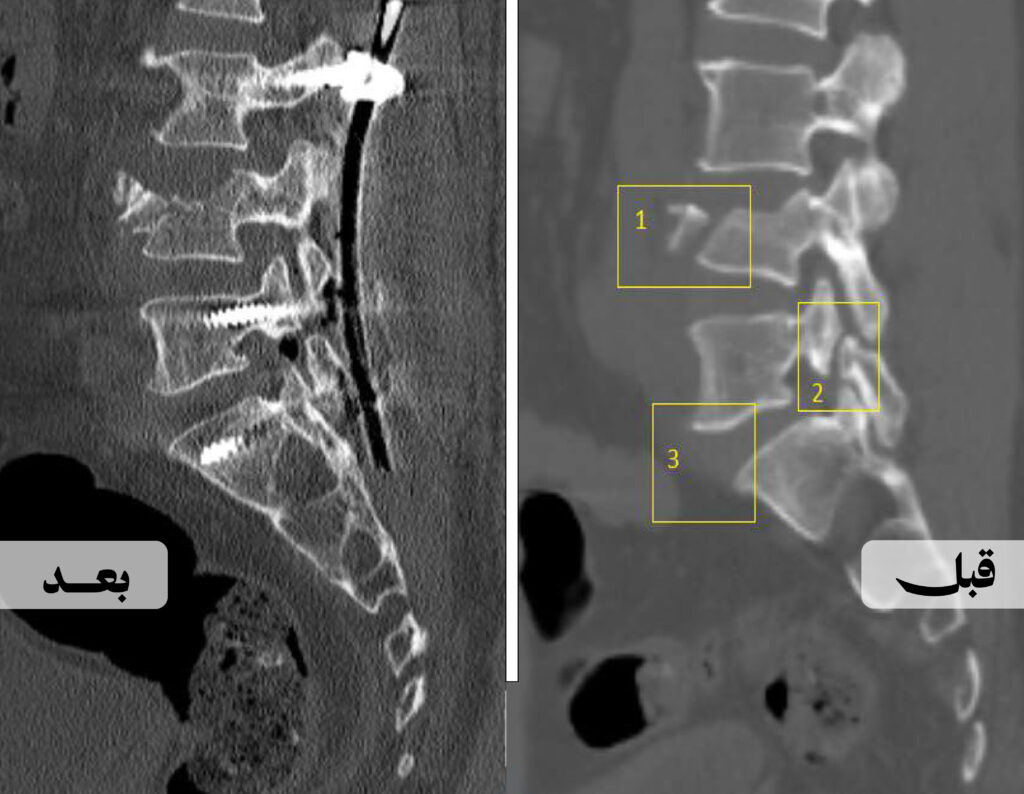

نجح فريق طبي في مستشفى الملك خالد عضو تجمع حائل الصحي في إجراء جراحة نوعية لمعالجة ثلاثة مشاكل في العمود الفقري خلال عملية واحدة لمستفيد في العقد الخامس من العمر، تعرّض لكسر في الفقرة القطنية الرابعة إثر حادثة سقوط.

وأوضحت الفحوصات وجود كسر, إلى جانب تزحزح سابق في أحد الفقرات وعيب خلقي بين الفقرة القطنية الخامسة والفقرة العجزية الأولى، ممّا شكّل تحديًا في استقرار العمود الفقري.

وأجريت جراحة متكاملة شملت تثبيت الكسر ومعالجة التزحزح والتشوّه الخلقي في ذات العملية، والتي تعد من الحالات النادرة، إذ إن الجمع بين هذه التدخلات في عملية واحدة يُقدَّر بأقل من 1٪ من جراحات العمود الفقري.